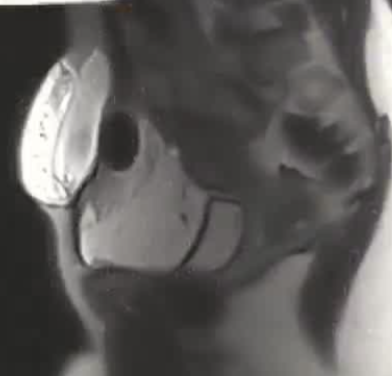

| 腹壁下病变 | MRI引导下 冷冻消融。装有热水的手套在皮肤表面保护皮肤 |

病灶位置:16个疼痛性目标病灶位于脐部(7/16,43.8%)、膈肌(4/16,25.0%)、腹股沟管(3/16,18.8%)和子宫肌肉层(即腺肌症,2/16,12.4%)。

影像引导方式:超声和横断面成像(CT或MRI)结合是最常用的影像引导方式(10/16,62.5%)。